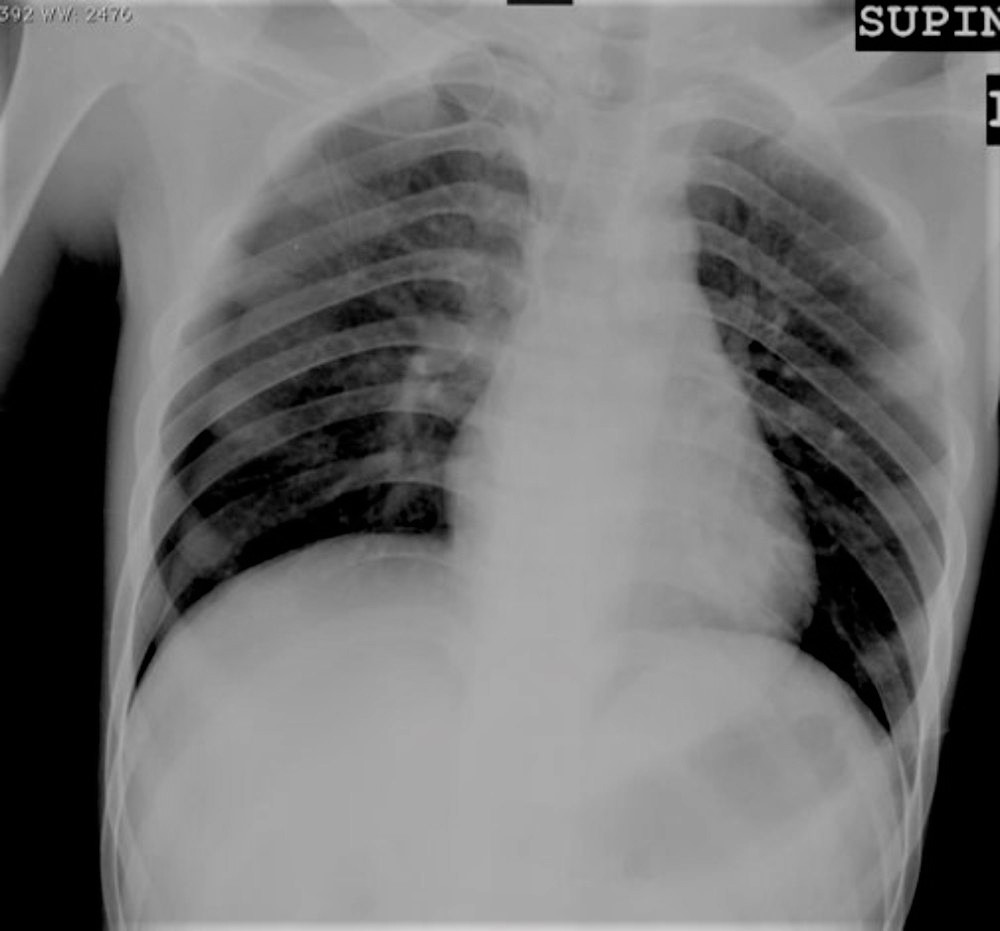

Dyspnea After Insertion of Central Venous Catheter Post category:Spot Diagnosis Post published:July 1, 2023 Share on Facebook Share on X (Twitter) Share on Pinterest Share on Email Share on Reddit Dyspnea after insertion of central venous catheter A 30 years old man presents with dyspnea after insertion of central venous catheter. What’s the Diagnosis ? FULL CASE AND ANSWER Share on Facebook Share on X (Twitter) Share on Pinterest Share on Email Share on Reddit Read more articles Previous PostA 60-year-old Woman with Blurry Vision in Left Eye Next PostGeneralized Pustular Eruptions You Might Also Like Patient with a 1-day history of fever, symmetric polyarthritis, abdominal pain, and hematemesis September 30, 2021 Asymptomatic, Widespread, Erythematous-to-Violaceous Papules and Plaques May 8, 2022 Hyperkeratosis, Papillomatous Plaques, and Loosely Adherent Crust on Legs December 15, 2021